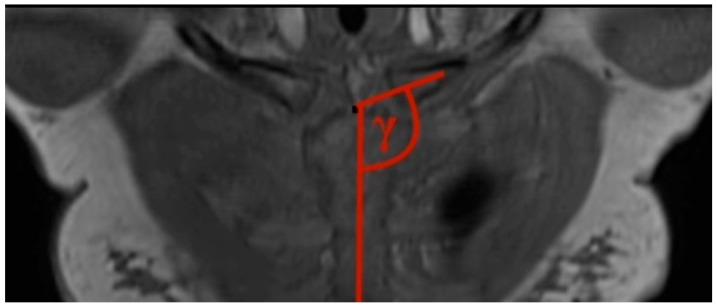

基于磁共振成像的胸锁关节和锁骨解剖结构的规范值:对1591名健康参与者的综合分析

The clavicle remains one of the most fractured bones in the human body, despite the fact that little is known about the MR imaging of it and the adjacent sternoclavicular joint. This study aims to establish standardized values for the diameters of the clavicle as well as the angles of the sternoclavicular joint using whole-body MRI scans of a large and healthy population and to examine further possible correlations between diameters and angles and influencing factors like BMI, weight, height, sex, and age. This study reviewed whole-body MRI scans from the Study of Health in Pomerania (SHIP), a German population-based cross-sectional study in Mecklenburg-Western Pomerania. Descriptive statistics, as well as median-based regression models, were used to evaluate the results. We could establish reference values based on a shoulder-healthy population for each clavicle parameter. Substantial differences were found for sex. Small impacts were found for height, weight, and BMI. Less to no impact was found for age. This study provides valuable reference values for clavicle and sternoclavicular joint-related parameters and shows the effects of epidemiological features, laying the groundwork for future studies. Further research is mandatory to determine the clinical implications of these findings.

尽管人们对锁骨及其相邻胸锁关节的磁共振成像了解甚少,但锁骨仍是人体中最易骨折的骨头之一。本研究旨在通过对大量健康人群进行全身MRI扫描,建立锁骨直径和胸锁关节角度的标准化值,并进一步研究直径、角度与BMI、体重、身高、性别和年龄等影响因素之间可能存在的相关性。本研究回顾了德国梅克伦堡-前波美拉尼亚州基于人群的横断面研究——波美拉尼亚健康研究(SHIP)的全身MRI扫描数据。采用描述性统计以及基于中位数的回归模型来评估结果。我们能够为每个锁骨参数建立基于肩部健康人群的参考值。研究发现性别之间存在显著差异。身高、体重和BMI的影响较小。年龄的影响较小或几乎没有影响。本研究为锁骨和胸锁关节相关参数提供了有价值的参考值,并显示了流行病学特征的影响,为未来的研究奠定了基础。必须进行进一步的研究以确定这些发现的临床意义。